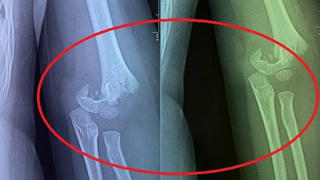

Sở GD&ĐT Hà Nội yêu cầu Phòng GD&ĐT quận Hai Bà Trưng và nhà trường xác minh, làm rõ việc trẻ bị ngã gãy tay tại trường mầm non Vườn trẻ thơ (250 Minh Khai).